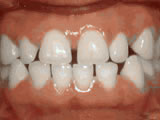

Missing lateral incisors

This patient's lateral incisors were congenitally missing. She had braces for 20 months to move the teeth into their correct positions, then the missing teeth were replaced with bonded "Maryland" bridges.